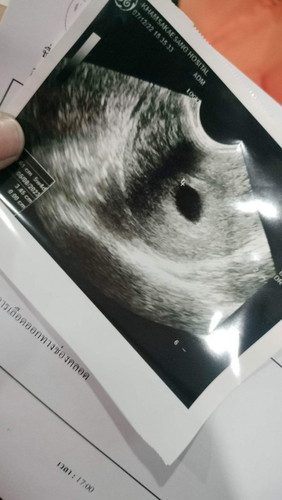

มีเลือดสีแดง2วัน วันที่3สีน้ำตาลค่ะ ไปหาหมอแล้วหมอบอกเสี่ยงแท้ง ,ท้องลม แต่ยังไม่แน่ใจค่ะ นัดตรวจวันที่12นี้ แอบเศร้าใจไม่น้อยเลย

ของเราตอน 5w เห็นแต่ถุงตั้งครรภ์เหมือนกันค่ะ เด็กยังไม่เป็นตัวเลยยังไม่เห็น พอ 6w มีเลือดออกสีน้ำตาลนิดหน่อย มีภาวะแท้งคุกคาม ซาวด์ทางช่องคลอด เห็นหัวใจเต้นแล้วค่ะ แต่ยังเป็นก้อนตัวอ่อนอยู่เลย พยายามทำใจให้สบายนะคะ พักผ่อนเยอะ ๆ ค่ะ 🥰